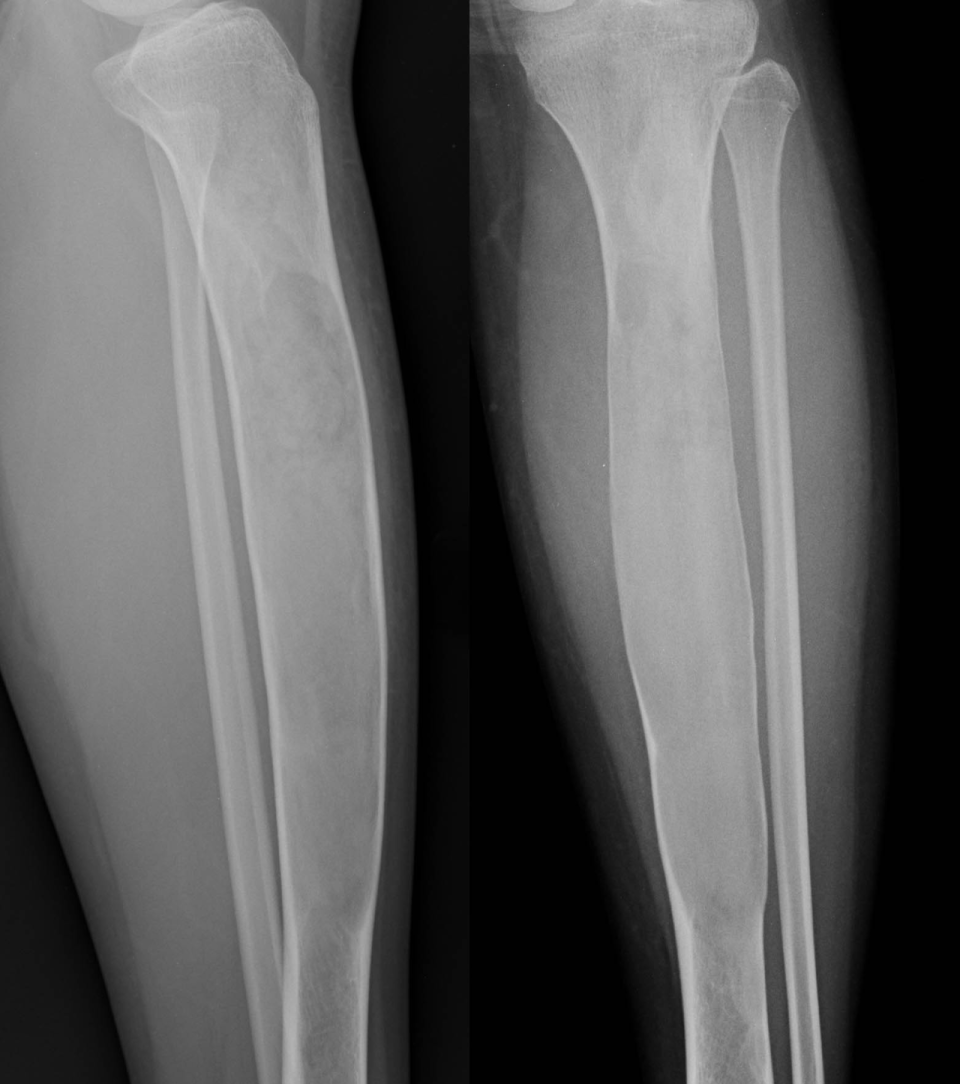

反应性骨增生是病变周围正常骨组织遭到肿瘤破坏后的反应骨,它并非骨肿瘤的特有征象,在骨创伤、骨感染时也可见到。良性肿瘤如骨样骨瘤、骨母细胞瘤等周围可见反应性骨增生(图 51、图 52)。原发于骨髓的恶性肿瘤如尤因肉瘤、骨淋巴瘤、骨恶性纤维组织细胞瘤等以及部分骨转移瘤均可在肿瘤周围产生大量反应性骨增生(图 53、图 54)。X 线平片或 CT 表现为松质骨内斑片状均匀骨化影或大量棉团样骨化影。亦有在多发灶性溶骨性破坏周围产生散在片状骨化影。

图 51.反应性骨增生:骨样骨瘤

图 52.反应性骨增生:骨母细胞瘤骨